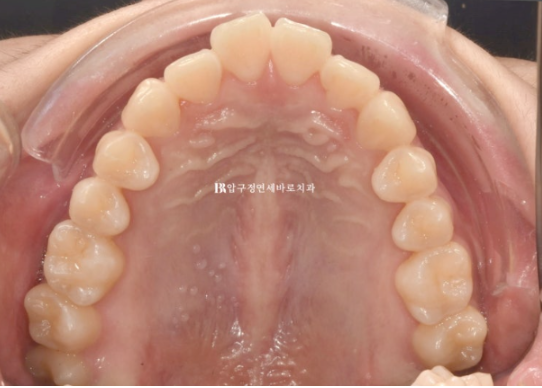

치료 전 - 치료 후 비교 사진입니다.

초진 24.02 이며 치료 종료는 24.07입니다.

24.02~24.07

좋은 교합은 유지가 되었고

토끼이빨은 정상 배열을 찾앗습니다.